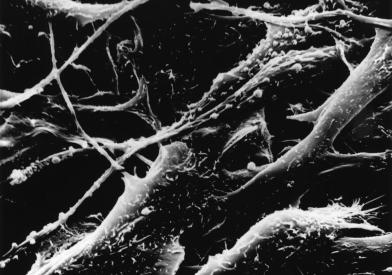

Skin cancer forms in tissues of the skin. Basal cell or squamous cell cancer forms in cells that do not make pigment. Both types usually occur in skin that has been exposed to ultraviolet radiation from sunlight or tanning beds, most commonly on the face, neck, hands, and arms and legs.